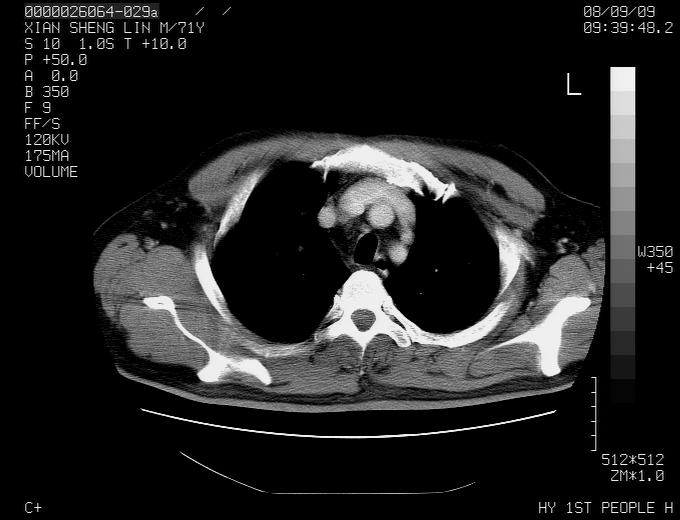

标题: CT15869:男性,71岁,因咳嗽而就诊,请讨论右上肺病变性质 [打印本页]

患者,男性,71岁,因咳嗽而就诊,

典型的右肺中心性肺癌并纵隔淋巴结转移

右肺中心性肺癌并纵隔淋巴结转移可能性大!

右肺中心性肺癌并纵隔淋巴结转移可能性大! 支持!

病灶中等程度强化 还是支持肺癌诊断

考虑右肺中心性肺癌并右肺门及纵隔淋巴结转移。

1,右肺中心型ca,气管隆突旁淋巴结转移。